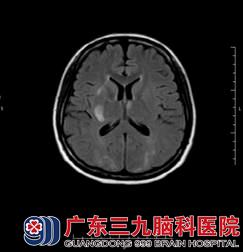

陈小姐在外院检查的MR提示颅内多发异常信号,神经内二科的医生主任结合其临床症状,考虑为子痫性脑病,不排除桥脑中央髓鞘溶解综合症;诊断初步考虑是可逆性脑后部白质病变? 静脉窦血栓形成?。陈小姐进一步完善了MR+增强+MRV检查,结果提示:1、双侧额顶枕叶、桥脑及中脑、左侧小脑半球、双侧基底节区及右侧侧脑室旁,左侧放射冠区多发病变。结合其病史,医生考虑为可逆性后部白质脑病综合症,建议治疗后复查;2、MRV检查示未见异常。

该病与高血压脑病,先兆子痫/子痫,急性肾小球肾炎,肾衰竭,系统性红斑狼疮等疾病相关。目前认为主要是颅内高灌注、血管内皮损伤及交感神经调节异常所致,通常表现为头痛(弥漫性钝痛,持续进展)、癫痫发作(双侧枕叶尖波的癫痫持续状态),意识障碍及视觉障碍四联征。其具有累及大脑后部白质的双侧对称的特征性影像学改变,这种改变在MR的T2压水像上最为明显(图1、图2),另外其病灶在MR弥散成像上的高ADC信号(图3)也可以与其他疾病相鉴别。